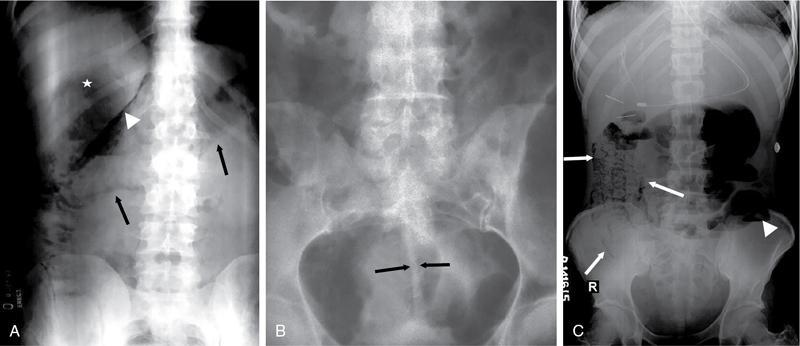

UNDERSTANDING THE ADULT ABDOMINAL RADIOGRAPH: TECHNIQUES AND INTERPRETATION Tanvi Modi Radiography of the abdomen is a common practice for the evaluation of abdominal organs. The anatomy and pathology of digestive, hepatobiliary and genitourinary systems can be assessed using radiographs, either as a stand-alone practice or as a primary imaging modality followed by contrast studies, ultrasound or cross-sectional imaging. In addition, abnormalities of the musculoskeletal or integumentary system can also be deduced on the basis of abdominal radiographs. This chapter intends to give an overview on the techniques and positioning in abdominal radiography as well as interpretation of normal and abnormal features. While superior imaging modalities such as ultrasound, computed tomography (CT), magnetic resonance imaging, capsule endoscopy and the likes have taken over abdominal imaging by and large, radiography still holds a pivotal role in certain situations and conditions, such as: The standard abdominal radiograph is taken in supine position and anteroposterior projection. This is also popularly known as the KUB (kidneys-ureters-bladder) radiograph. Previously, supine as well as erect radiographs were performed in all patients; however, this is not commonly done due to high-radiation dose. For all indications of abdominal radiography, including acute abdomen, supine radiographs are sufficient in terms of radiographic diagnosis, with the exception of perforation for which an erect chest or lateral decubitus radiograph can be performed if there is clinical suspicion. Patient should lie supine on the imaging table with median sagittal plane at right angles to the table and coincident with the midline of the table (Fig. 7.1.1.1). The body is divided into equal right and left halves by the median sagittal which passes through the sagittal suture of the skull. Pelvis should be adjusted so that the anterior superior iliac spines are equidistant from the table top. Gonadal shields, in the case of male patients, should be placed with the upper edge of the shield at the level of pubic symphysis. Although rarely used for female patients, these should be positioned between the anterior superior iliac spines and the pubic symphysis. The centre point of the image receptor should be approximately located at a point 1 cm below the line joining the iliac crests. The X-ray beam should be in a vertical direction, perpendicular to the table top and image receptor at the centre point. Collimation should be such that the soft tissue and subcutaneous region along lateral aspects of the abdominal cavity should be covered within the image. Also, the superior extent involving diaphragm and inferior extent involving the inferior pubic rami is important to look for any lower chest pathologies or any inguinal hernia. 35 × 43 cm (14 × 17 inches) in portrait orientation. On an average, abdominal radiograph exposes a patient to a dose of approximately 1.5 mSv, which is equivalent to 75 chest radiographs or 1/6th dose of a standard CT of the abdomen. The entrance skin dose is approximated to be 4 mGy. At such an effective dose, the additional lifetime risk of fatal cancer is 1 in 30,000. The exposure time is kept short. Patient is asked to exhale completely and hold their breath, with exposure taken at this point of full expiration to ensure imaging of abdominal organs in their natural positions. Modifications of this technique can be made depending on patient habitus and clinical condition. Kilovoltage peak (kVp) should be set to allow adequate visualization of abdominal soft tissue structures as well as semiopaque renal and biliary calculi. Average kVp is set at 70–85 kV. 102 cm (40 inches) Grids are commonly used to reduce scatter radiation. Placement of side marker on the image receptor at the time of radiographic exposure is essential. Bowel pattern depiction should be such that there is minimal lack of sharpness. Standard guidelines for abdominal radiography dictate that the radiograph should extend from the diaphragm up to the level of inferior pubic rami and must include the lateral abdominal wall musculature. The abdomen is divided into four quadrants on the basis of two perpendicular lines (Fig. 7.1.1.7). The vertical line passes through the mid sagittal plane and crosses the umbilicus and symphysis pubis. The horizontal line is a transverse line across the umbilicus at 90 degrees to the vertical line and is situated at the level of L4–L5 intervertebral disc. The quadrants are as follows: Another division system is dividing the abdominopelvic cavity into nine regions using two vertical and two horizontal planes (Fig. 7.1.1.8). The vertical planes, also known as the right and left lateral planes, are parallel to the midsagittal plane between midline and anterosuperior iliac spines on either side. Of the two horizontal planes, the upper transpyloric plane is at the level of lower border of L1 and the lower transtubercular plane is at the level of L5. The nine regions are: On a standard radiograph, the exposure should be such that the stomach, bowel loops, outlines of liver, spleen, kidneys, psoas muscles should be well identified. Also, lumbar transverse processes should be seen. Arch of the pubic symphysis should be visible to evaluate bladder region. A well-centred film without rotation will demonstrate bilaterally symmetrical lower ribs, iliac wings, ischial spines and obturator foramina. Different structures seen on an abdominal radiograph can be classified into five basic densities: Identification of different structures depends on the relative degree of contrast between their densities. The demarcation is clearer in chest and is diminished in abdomen due to relative similar soft tissue density of various structures. On a normal radiograph, relatively large amounts of gas in stomach and colon with minimal small bowel gas can be seen. Further, colonic gas can vary from negligible to extensive, mimicking obstruction pattern; however, usually the gas is enough to delineate colonic haustral pattern. Faecal matter gives a mottled appearance to colonic gas. Short-air fluid levels on an erect radiograph may be seen even in normal cases. The normal appearance of small bowel loops on an abdominal radiograph follows the rule of threes: Stomach is seen in the left upper quadrant and is visualized when distended with air. It is commonly seen extending from T11 to L2 level. Common feature identifying the stomach is the fundal gas which is usually seen as an air fluid level within the gastric lumen. Small bowel loops are distributed to the centre of the abdominal cavity and large bowel loops are peripheral. Duodenum is predominantly situated in right upper quadrant. It extends to left upper quadrant in the region of duodenojejunal flexure. Jejunum occupies the left upper and lower quadrants and is easily identified due to the presence of thick, numerous, closely spaced valvulae conniventes (Fig. 7.1.1.9A). The ileum occupies both lower quadrants and extends into right upper quadrant. Ileum has few and less prominent valvulae as compared to jejunum (Fig. 7.1.1.9B). Ascending and descending colon are retroperitoneal and have relatively fixed positions along lateral aspect of the abdominal cavity on either side. Transverse and sigmoid colon, on the other hand, may have a variable position due to their mobility along mesocolon and redundant pattern. These can be identified with confidence on account of haustrations and faecal matter (Fig. 7.1.1.10). Haustrations are usually well seen in ascending and transverse colon and poorly delineated beyond splenic flexure. Caecum is in the right lower quadrant, though it may be mobile or pulled up. Rectal gas is usually seen in the midline at the level of pelvis and its presence rules out large bowel obstruction. All these positions may vary due to anatomical conditions such as malrotation or pathological conditions, for example volvulus. Liver, spleen and renal outlines cannot be completely traced with precision due to the overlap by bowel loops. On a frontal projection, the liver appears as a triangular structure occupying right and left hypochondrium and epigastric region. Occasionally, the right lobe may be seen extending lower than the right renal shadow. This is a normal variant known as Reidel’s lobe. Gall bladder is situated in the posterior and inferior region of the liver and any pathology of the gall bladder should be looked for in this region. On a lateral radiograph, the gall bladder is anterior to the midcoronal plane. This helps in distinguishing gall bladder calculi from renal calculi, which will be more posteriorly situated. Spleen is seen in left upper quadrant/left hypochondrium, flushed to left lower ribs and left hemidiaphragm. Pancreas is present in the epigastric region (right and left upper quadrants) and is usually not identified in the absence of a pathology. The kidneys are bean-shaped retroperitoneal organs which are seen on either side of the vertebral column and lateral to psoas muscles. Due to the presence of liver on the right side, this kidney is slightly lower in position as compared to its contralateral counterpart. The visualization of kidneys on radiographs is facilitated by the surrounding fatty capsule. Kidneys lie between T11–12 and L2 level, with left kidney 1 cm higher than the right. Psoas muscle shadow can be normally seen along lateral aspect of lumbar spine bilaterally and is mildly concave (Fig. 7.1.1.11). Abdominal wall muscles are not routinely assessed on radiography; however, inclusion of lateral abdominal wall (muscles as well as subcutaneous plane) is a must while performing radiography. The flank stripe or the properitoneal fat stripe is a fat density linear concavity seen along lateral abdominal wall (Fig. 7.1.1.11). It is bound by the paracolic gutters and air-filled ascending and descending colon. All the solid organs in the abdomen are identified due to the fat density outlining them. Distortion of these fat lines helps in identifying organomegaly or focal mass lesions. The dome of urinary bladder is outlined by fat, which aids in differentiating its density from other soft tissue structures of the pelvis. Not all calcifications seen on abdominal radiograph are abnormal. Some may depict age-related changes such as vascular calcifications involving abdominal aorta, pelvic vessels, splenic artery in the region of left upper quadrant. Within the pelvis, phleboliths may be seen and mistaken for urinary calculi. Assessment of lumbosacral spine, iliac bones and femoral heads can be made on the basis of plain radiography. Degenerative changes may be commonly seen. Lower ribs can also be evaluated for pathologies. Dilated small bowel loops with rounded soft tissue density in midline over umbilical region suggests obstruction secondary to umbilical hernia. Pneumoperitoneum must be looked for in all cases of acute abdomen. While erect chest and left lateral decubitus radiographs can detect even 1 mL of free air, there are multiple signs on supine radiograph to suggest this diagnosis, for example Rigler’s sign, falciform ligament sign, football sign (Figs. 7.1.1.24 and 7.1.1.25). Retroperitoneal perforation may demonstrate air outlining psoas muscles and retroperitoneal organs. Small amount of free air may persist in the abdominal cavity up to 3 weeks after surgery, although it usually resolves within a week. Clinical history is important in such cases. Air foci within the bowel wall may represent bowel ischaemia/strangulation. Linear gas patterns in right hypochondrium may be due to two causes, that is pneumobilia and pneumoporta. The former can be seen normally postbiliary surgery, sphincterotomy, ERCP or in the case of abnormal fistulous communication between bowel and biliary tree (Fig. 7.1.1.26A). Pneumoporta (Fig. 7.1.1.26B) is a red flag and warrants further investigation to look for conditions such as mesenteric ischaemia and toxic megacolon. Pneumobilia is more centrally located whereas air shadows in pneumoporta are seen reaching up to periphery of liver. Air foci over renal shadows (Fig. 7.1.1.27), gall bladder or pancreas, in the absence of recent procedural history, suggest fulminant infection and mandate urgent intervention. Central midline calcific foci between T9 and T12 vertebrae can be attributed to calcific pancreatitis (Fig. 7.1.1.28). In the left upper quadrant, areas of calcification seen involving a shrunken spleen may be seen in autosplenectomy. In right upper quadrant, calcified gall stones may be seen. These tend to be small, multiple, uniformly circumscribed and ring-like in appearance with central translucency (Fig. 7.1.1.29A). Mercedes Benz sign, a triradiate pattern of gas lucency, is associated with gallstones. In contrast, renal calculi are more commonly solitary, irregular, of homogenous density, conform to renal calyceal or pelvic outline (Fig. 7.1.1.29B) and are sometimes of staghorn configuration. On lateral view, the gall stones are more anteriorly located as compared to renal calculi, which may be partly superimposed on lumbar vertebrae. Ureteric calculi tend to overlap bony structures such as lumbar transverse processes (Fig. 7.1.1.29B) or sacroiliac joints. Extensive or patchy, curvilinear calcification of gall bladder wall is known as porcelain gall bladder which is often associated with malignant transformation. Calcification involving adrenal glands may be secondary to infection or haematoma, or a congenital condition known as Wolman’s disease where there is bilateral involvement. Discontinuous discrete midline tram track calcification in the abdomen may indicate atherosclerotic changes in abdominal aorta and branch vessels. However, when the calcification is in a globular pattern and seen below the level of L2 vertebra, aortic aneurysm should be suspected (Fig. 7.1.1.30). Appendicoliths, though not commonly seen, may sometimes be detected in right iliac region. Pelvic calcifications: vesical calculi, distal ureteric or vesicoureteric junction calculi, calcified fibroids, ovarian dermoid with tooth-like calcifications (Fig. 7.1.1.31) may be the cause of abdominal pain and should be diligently looked for. Vesical calculi are usually more large and central in location whereas calcification due to fibroids may be more lateral. Schistosomiasis is another cause of bladder wall calcification, as is calcification of bladder tumours. Phleboliths tend to be bilaterally symmetrical, with a lucent centre unlike ureteric calculi. While it is believed that phleboliths are located below the level of ischial spines and ureteric calculi above, this is not always true and should be confirmed with CT. Fluid may collect adjacent to properitoneal fat line, forming a linear soft tissue density separating the fat line from the ascending or descending colon. Hellmer’s sign demonstrates medial displacement of lateral edge of liver (hepatic angle), due to fluid collection or ascites. Gross ascites may appear as generalized abdominal haziness or diffuse increased density of pelvis. Abscesses can involve any solid organ and in such cases may be difficult to demonstrate on plain radiography alone. Enlargement of organ or faint gas densities within can be suggestive of the same. In the case of peritoneal abscess, mottled density due to air, fluid and necrotic contents point towards this diagnosis, especially in right iliac fossa in association with appendicitis. Retroperitoneal abscess, similar to any retroperitoneal mass, may cause displacement of retroperitoneal structures (Fig. 7.1.1.32). Subdiaphragmatic abscesses may show concomitant ipsilateral pleural effusion (Fig. 7.1.1.33). These should be differentiated from Chilaiditi syndrome. Fluid and soft tissue lesions present with the same density on radiographs. While it is difficult to characterize the lesion and organ of origin, clues for the same can be provided by organomegaly (Fig. 7.1.1.34), distortion of fat surrounding solid organs, displacement of bowel loops or solid organs. For example, a retroperitoneal lesion may cause anterior or inferior displacement of kidney, a pelvic mass may cause upward displacement of small bowel loops. Different densities such as fat or calcification may help in identifying organ of origin (e.g. fat and tooth densities seen in ovarian dermoid). Convexity of margins of psoas muscle on an abdominal radiograph can be due to haematoma, abscess or intramuscular tumour. Radiographs are performed for the initial diagnosis of foreign body in the abdomen including type, number of foreign bodies, location, size and shape (Fig. 7.1.1.35). Radiolucent foreign bodies such as wood, plastic, chicken bones will not be easily identified on radiography. Low kVp (65–70 kVp) can increase contrast and help identify these objects. In addition to an abdominal radiograph, chest radiography is also performed to exclude aspiration or oesophageal location of foreign body. Ingested or introduced foreign bodies may cause complications such as obstruction, perforation, fistula formation and sepsis. Hence, once their presence is confirmed, follow up radiography must be performed until they are eliminated. One must look for fractures/dislocation injuries involving the vertebrae or pelvic bones, especially after history of trauma. Lucent expansile lesions or sclerotic bony deposits which represent neoplasms, absent pedicle sign in cases of metastasis, metabolic bony changes such as rugger jersey appearance, Paget’s disease, arthropathies such as ankylosing spondylitis with bamboo spine appearance and sacroiliitis (Fig. 7.1.1.36) are some of the conditions which may be diagnosed based on an abdominal radiograph. Overlap of bowel loops over iliac blades may lead to a misdiagnosis of lucent lesions and should be evaluated with caution. Basal pneumonia may be the cause of acute abdominal pain and should be looked for in abdominal radiography. Similarly, pleural effusion, pericardial effusion, calcified pleural plaques, achalasia, interstitial fibrosis are few other findings that can be seen in lower chest on an abdominal radiograph. Basilar atelectasis can give a deceptive appearance of pneumoperitoneum (Fig. 7.1.1.37). Surgical clips, commonly in right hypochondrium after cholecystectomy, drainage tubes, ventriculoperitoneal shunts, femoral line catheters, IVC filters, stents (vascular, renal, biliary) (Fig. 7.1.1.38), stoma bags, contraceptive devices are some structures that may be seen in an abdominal radiograph. Correct knowledge of patient history and normal locations of these structures prevents misdiagnosis. Certain artefacts may be projected upon the radiograph due to surface structures such as trouser buttons, body piercing, sequins over clothing and should not be considered as a pathology. Multiple skin surface nodules in cases of neurofibromatosis, soft tissue focal swellings, such as abscesses, lipomas, haematomas, desmoid tumours and malignant lesions may be incidentally seen on radiography. These can be further evaluated using ultrasound or CT. Subcutaneous emphysema is another finding that may be seen in lower abdominal wall secondary to retroperitoneal perforation or diffusely along abdominal wall in the case of bowel perforation (Fig. 7.1.1.39). Foreign bodies such as bullets and pins may be seen lodged in abdominal wall. A systematic approach to abdominal radiographs is important for accurate diagnosis as follows: Despite the development of newer techniques for imaging of the abdomen, plain radiography still holds an important place in the initial assessment of acute abdomen. Positive and negative findings on an abdominal radiograph can direct further investigation. Ideal positioning, recognition of normal appearances and keen scrutiny for pathologies is a sine qua non for radiologists reading a plain film of the abdomen. OESOPHAGOGRAM Padma V. Badhe, Vikram Reddy, Sultan Moinuddin Shaukatali, Zillani Alam, Ravi Varma, Abhishek Bairy, Dasari Ravikiran, Revati Tekwani, Soniya Patankar, Megha Nair, Gautham Shankar Oesophagogram is the process of obtaining radiological images and simultaneous motion recording to evaluate function and disorders of pharynx, oesophagus and proximal stomach. Oesophagogram is usually done primarily to evaluate dysphagia. Some of the common indications are oesophageal motility disorders, strictures, gastro-oesophageal reflux disease (GERD) and suspected masses. It can also be used to detect uncommon anomalies like vascular rings/slings and aberrant anatomy. It also helps to evaluate further in cases where there is inability to pass upper GI scope. Double-contrast oesophagogram is mainly indicated in early mucosal disease like erosion, polyp, infection and tumours. If a motility disorder is suspected, dynamic technique (e.g. videofluoroscopy) is used for dysphagia or aspirations in cases of stroke, neuromuscular disorders, post head and neck surgery or radiation. Barium oesophagogram is contraindicated in suspected cases of perforation and tracheoesophageal fistula, aspiration, rarely if there is hypersensitivity to barium suspensions. It is also contraindicated in suspected oesophageal perforation where a water-soluble contrast agent is more suitable. However, ionic water-soluble contrast agent is better avoided in cases of aspiration or fistula with airway. The contrast examination of the pharynx is dangerous in cases of acute epiglottitis and must be ruled out on plain radiograph. An 80% w/v barium suspension is used in full column views. However, 200%–250% w/v barium suspensions is usually required for mucosal relief films. The barium sulphate mixture is fed to the patient either by spoon, by glass, or through a drinking straw, depending on its consistency. In videofluoroscopy, the pharyngeal phase of swallowing is usually safer with barium pudding than with thick barium and safer with thick barium than with thin barium. However, if the major abnormality is poor pharyngeal contraction leading to stasis in the piriform sinus (and epiglottic tilt is normal), a thin liquid is safer. Epiglottic motility is better assessed with thin barium because thick barium often obscures the epiglottic tip. Fluoroscopic equipment capable of cine fluoroscopy and capability for rapid sequence spot images (high frame rate) is needed for this examination, Barium suspension, straw, glass, Lead apron and radiation protective equipment. The patients are instructed to fast after midnight before the day of the examination. The pharynx should be made as dry as possible during the examination as high-density barium adheres to dry pharyngeal mucosa. Activities like smoking, chewing gum and lozenges must be abstained before the procedure as they impair barium coating by increasing the salivary secretion. Regular oral medications must be taken with sips of water; however, insulin must be skipped on the morning of examination. The major principles of a good oesophagogram includes mucosal coating, distension and projection. A routine oesophagogram consists of screening of the oral, pharyngeal and oesophageal phases of swallowing, single and double-contrast examination of pharynx, single contrast, double-contrast and mucosal relief views of the oesophagus. In cases of dysphagia, the examination is tailored depending on whether the symptoms are either pharyngeal or oesophageal and initial fluoroscopic findings. If patients’ symptoms are suggestive of oral or pharyngeal disorder then pharynx is evaluated first. Similarly, if patient is suspected to have thoracic oesophageal disease then, double-contrast examination of the oesophagus is performed before the pharyngeal evaluation. During an oesophagogram the positioning of the patient varies according to the type of examination (Table 7.1.2.1).